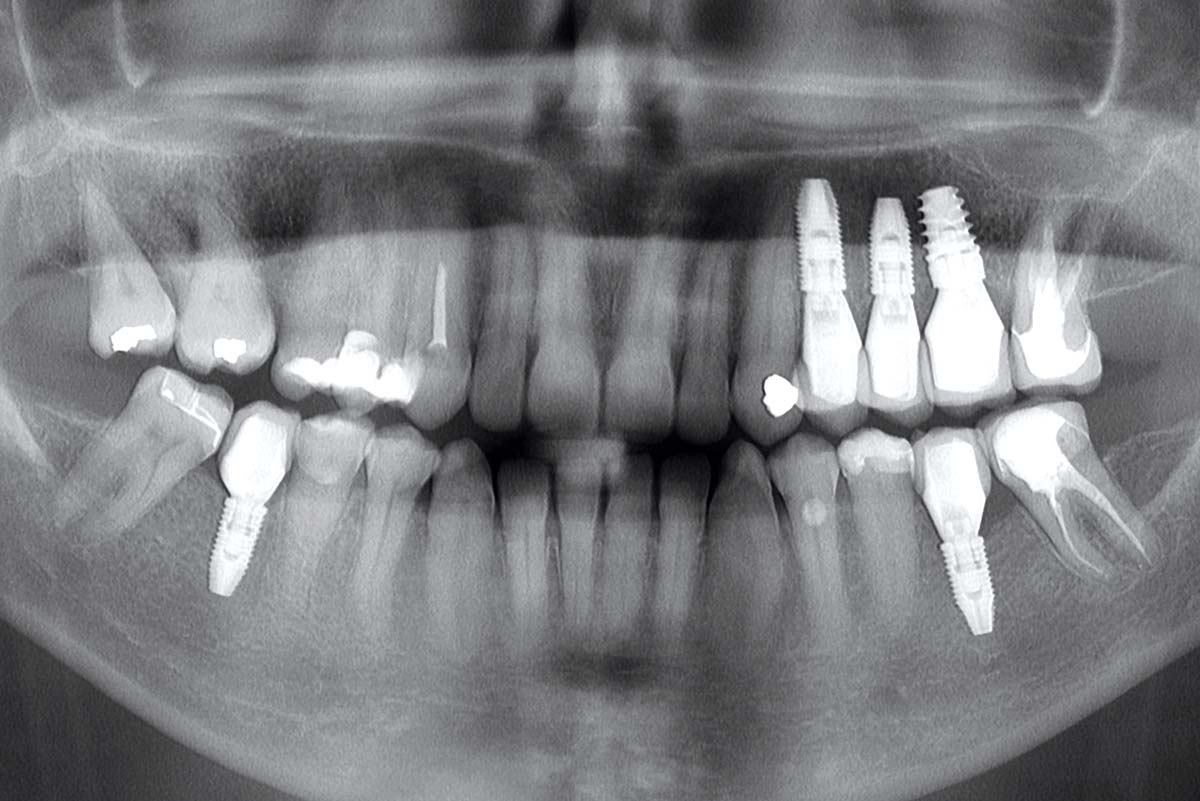

12/13 - Control OPG after 7 months

Multiple socket preservation in the maxilla with collacone® max – Dr. D. Jelušić